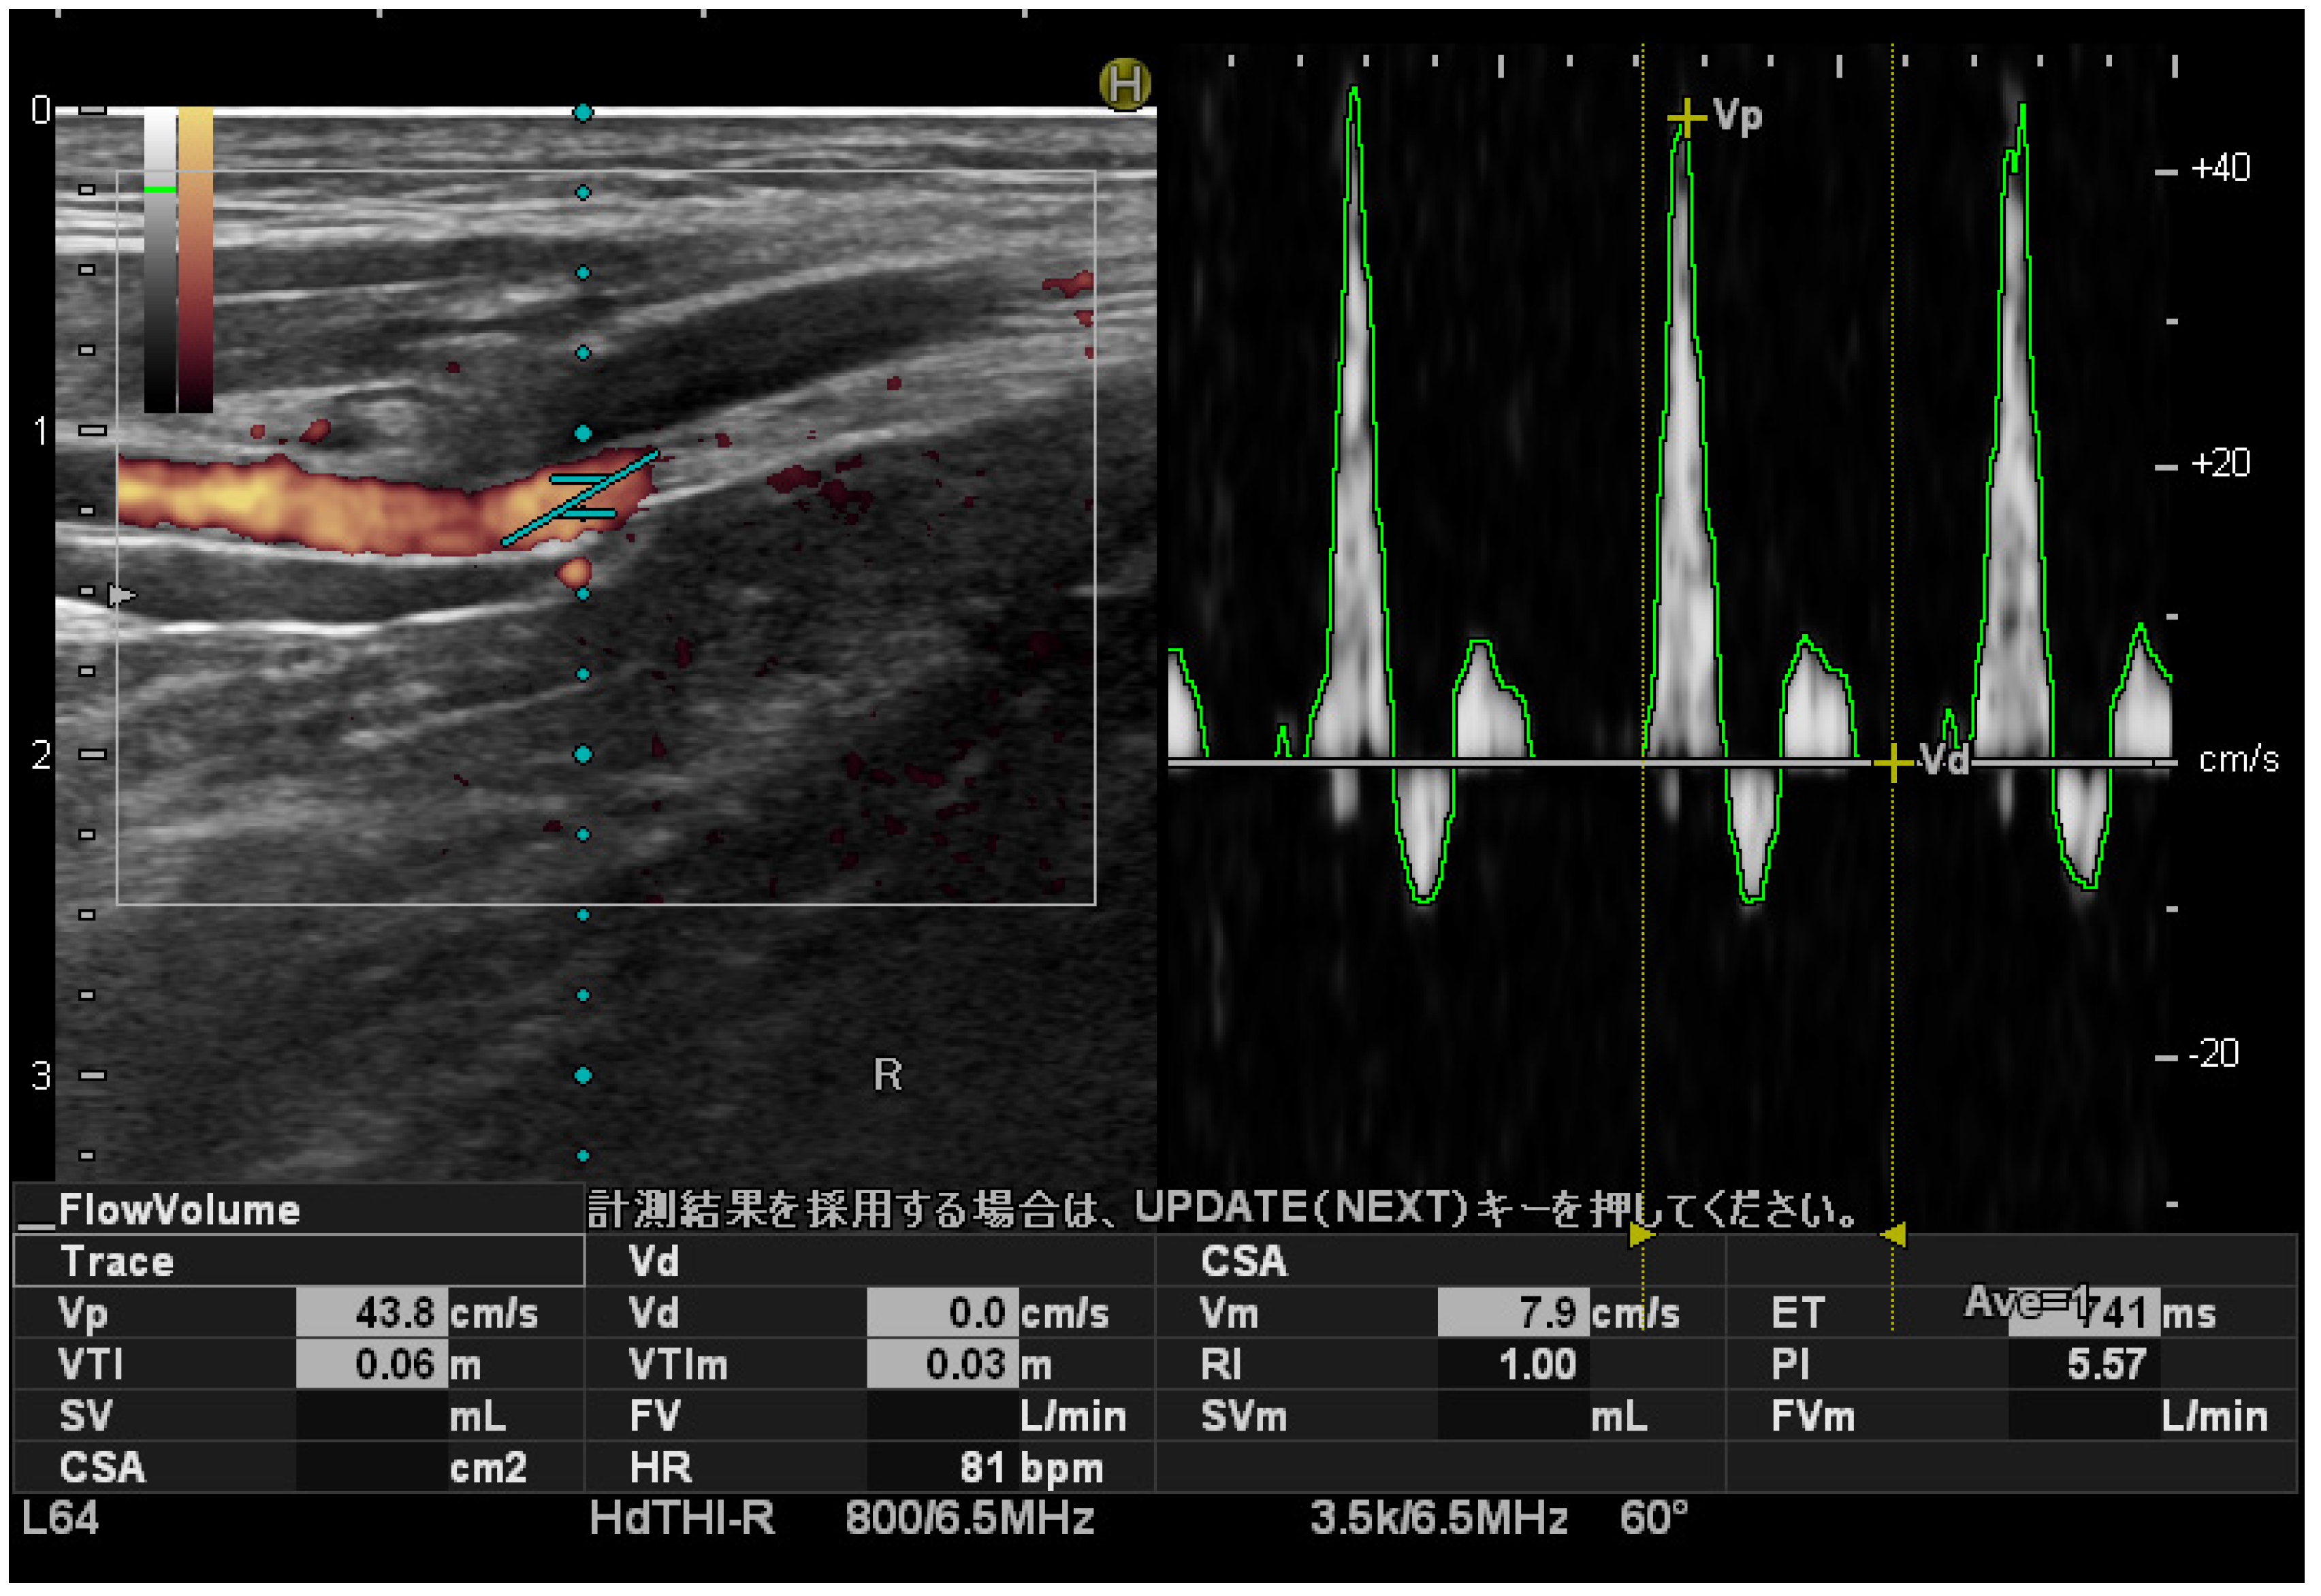

3.2. Comparison of PSV between Groups and Differences between the Left and Right Sides

The affected-side PSV in the PHP group was significantly higher than that in the control group (affected side: 44.1 ± 13.1 cm/s; control group: 32.7 ± 5.9 cm/s; p < 0.05, effect size: 0.50). No significant difference was observed between the two groups regarding the left–right difference (PHP group: 7.1 ± 9.8 cm/s; control group: 3.7 ± 3.3 cm/s; p = 0.12, effect size: 0.29) (Figure 2).

Figure 2.

Comparison of PSV between groups and differences between the left and right sides.